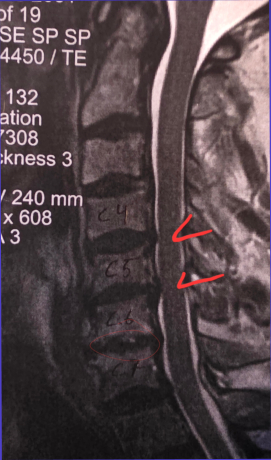

The time has come to take a break from the shop for a few weeks as I have neck surgery coming up in a few days. The surgeon will be fusing C4, C5, C6, and C7 vertebrae in hopes of releasing encapsulated nerves so that my left shoulder can work again. For the past 2.5 months I lost use of the shoulder 100%: best way to picture it is to glue your elbow to your rib and you can only mover the lower arm anywhere it wants, kind of like a T-Rex. :-) Otherwise my arm has not been able to move forward, outward, or upward. The good news is that I have had zero pain…the only time it’s been real fun is when I lost my balance twice to my left and had no arm to stop me from falling into the wall or whatever was in my path. I pitied those objects as I’m a big lug. No other harm done, except maybe that which I hit. ***NEW PAGE: “Gift Ideas”, which are non-flute items I’ve created…I love various forms of art and photography, and I have a 2026 calendar of my wildflife photography as well as 2 different sets of five notecards from Haywood County. One is of scenic views, and the other is of wildlife. The cards are 5” x 7”, providing a good amount of space for writing longer notes. These have been only recently produced, so have not yet hit the market, so to speak. Admittedly I’m still trying to nail down the price since the price of shipping is such a bugger anymore, but I’ll post that as soon as I can find affordable mailers and have the shipping priced out. The calendar features only five critters from Haywood County, the rest from other places. The cover is one of my favorite animals of all, the Barred Owl, this one sitting quite often right by home, All pictures enlarge nicely when you click on them, so you can see more of the details. The cards have additional information on the back of each, FYI. # # # I’m doing my best to stay on top of the MOUNTAINOUS emails full of too much spam, but if you don’t hear from me in a timely manner please gently nudge me again. The amount of emails is stupid, and building constantly…I clear out up to 200 junk emails every day, and heaven forbid a skip a day or two. Eegads… Knowing me, I’ll be sneaking in to the shop even if to try and clean it up and organize things better as I convalesce. Lord knows there is almost no limit to what needs to be done down there, and I have some stunning wood I can’t wait to get cutting. On top of more Spalted Tamarind, I have some figured Cheche and a new wood that I’d never heard of, Muirapixuna. It’s very much like chocolate brown Ebony, but a totally different species, from Brazil. Stay tuned! Browse and enjoy! Email with any questions. Bob Child weatherflute@yahoo.com